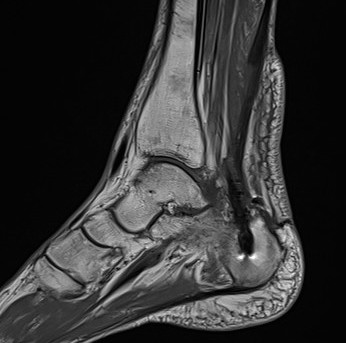

MRI

Partial tearing at insertion with retrocalcaneal bursa

Tendon thickening, Haglund's deformity and retrocalcaneal bursa

MRI grading

- Grade I: 6 - 8 mm thickening

- Grade II: > 8 mm tendon thickness with < 50% tendon degeneration

- Grade III: > 8 mm tendon thickness with > 50% tendon degeneration